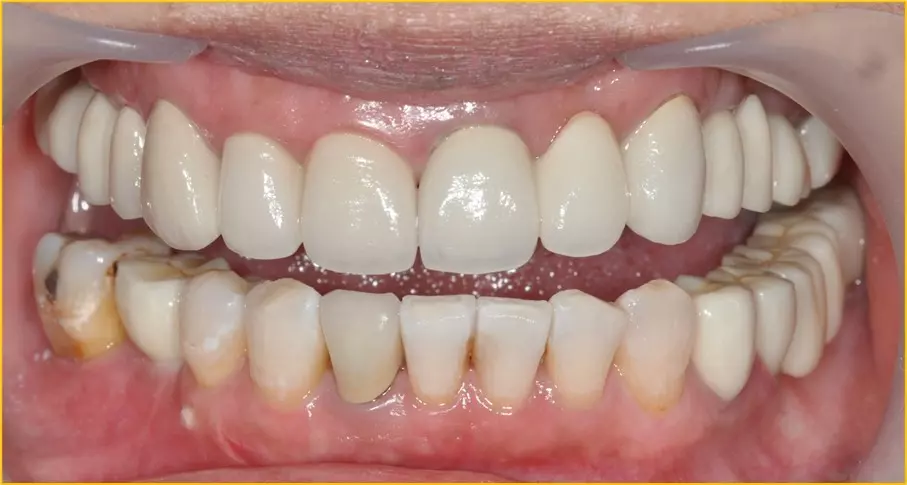

↑治療後漂亮整齊的牙齒